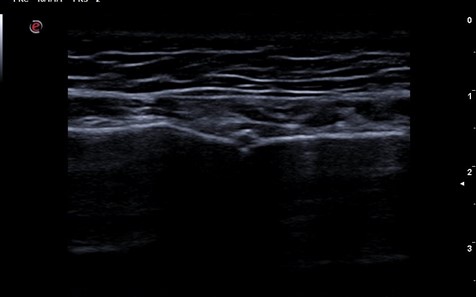

A través de varios casos clínicos se ha hecho una experiencia formativa en el C. Salud tras revisión de la literatura al respecto, se hace una sesión clínica teórica con los distintos diagnósticos diferenciales y hallazgos ecográficos y otra práctica para mostrar cómo explorar la pared torácica. Entre los casos atendidos encontramos: 3 costocondritis, una contusión pulmonar, fractura de esternón a los 15 días tras accidente tráfico, diagnóstico diferencial costocondritis vs metástasis pulmonar en paciente con cáncer de mama, varios casos de artritis de la articulación esternoclavicular, fracturas costales, seromas, hematomas, diagnóstico diferencial con linfomas, abscesos, etc.

El dolor de la pared costal supone uno de los retos más desafiantes en nuestras consultas, debido a que las causas isquémicas como las no isquémicas comparten clínica y síntomas. La ecografía clínica se posiciona como una herramienta clave para mejorar el diagnóstico diferencial del dolor torácico tanto en centro de salud como en las urgencias hospitalarias, por ser inocua, accesible y en el momento de la exploración.